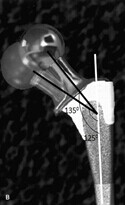

第二点,假体的选择。国外的中心往往有多种角度的假体供医生选择,而反观国内,可供中国医生选择的假体不足,大多数都是固定的135°颈干角假体,有什么,用什么。而我们知道正常人颈干角范围在125°-137°之间,平均为127°。事实上,Charnley 在设计髋关节柄的时候,是计划解剖重建颈干角的所以最早期的假体是125°颈干角的,以此精确重建Offset,但当时的假体材料不过关,强度不够,于是采用了大颈干角,小偏心距的135°。重建正常的Offset需要有更多合适的假体作为支撑。有限的假体型号、再加上没有正确的术前计划不足以重建正常的偏心距。